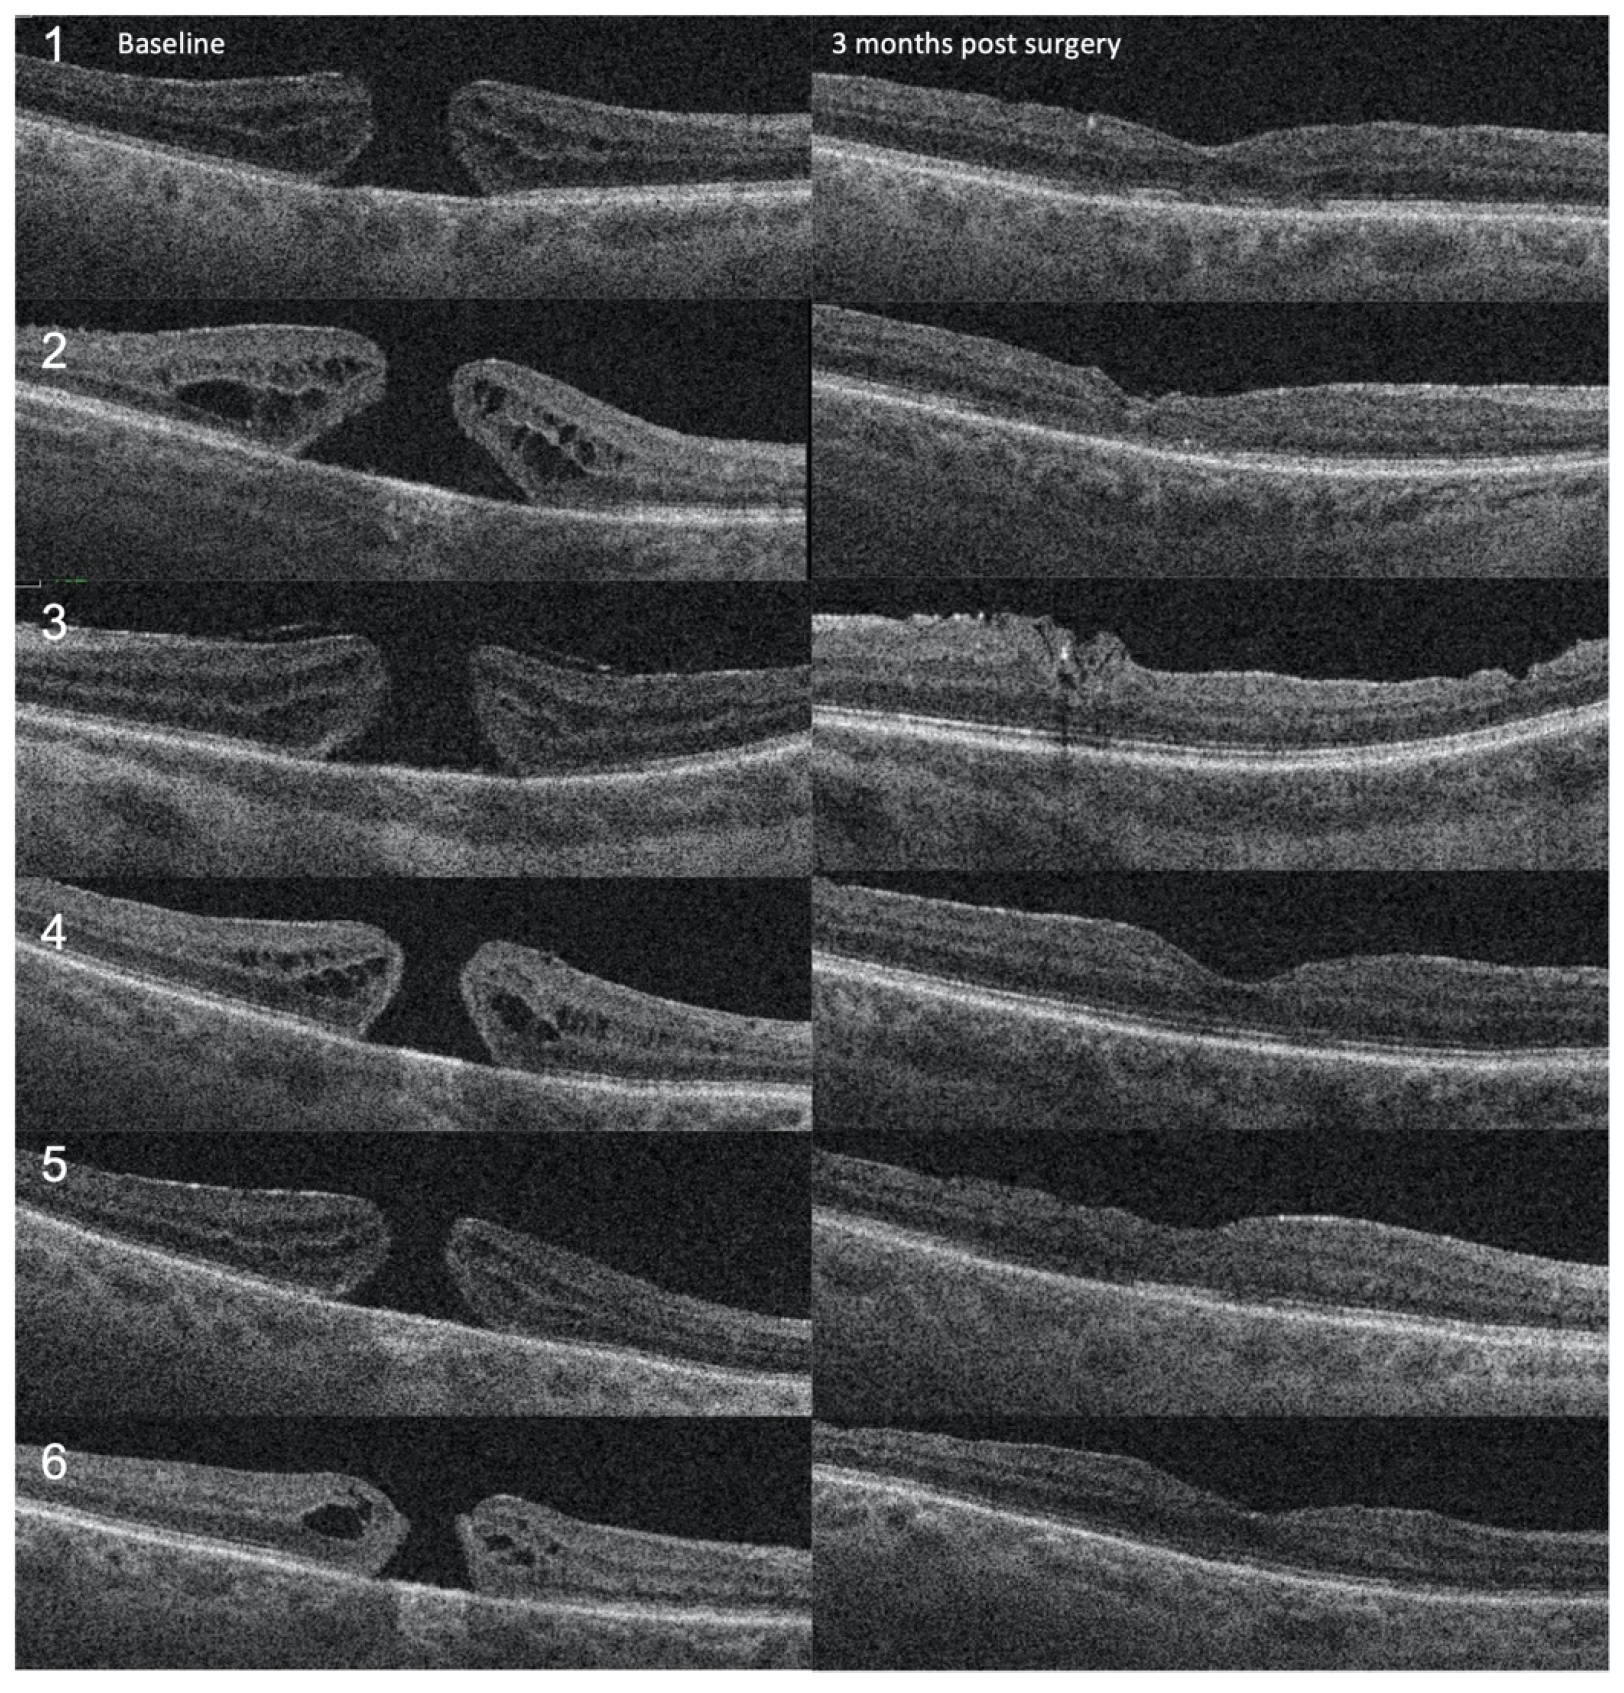

3. Results

| Pt. | Age | Gender | Duration of Symptoms | Minimum Hole Size (μm) | Basal Hole Size (μm) | Preoperative BCVA (LogMAR) | Postoperative BCVA (LogMAR) |

|---|---|---|---|---|---|---|---|

| 1 | 71 | M | 18 months | 549 | 1224 | 0.7 | 0.3 |

| 2 | 84 | F | 24 months | 526 | 1748 | 0.7 | 0.5 |

| 3 | 56 | F | 6 months | 602 | 1343 | 0.7 | 0.7 |

| 4 | 71 | F | 3 months | 443 | 1063 | 0.3 | 0.0 |

| 5 | 73 | M | 6 months | 424 | 1169 | 0.7 | 0.5 |

| 6 | 72 | F | 6 months | 337 | 703 | 0.7 | 0.4 |